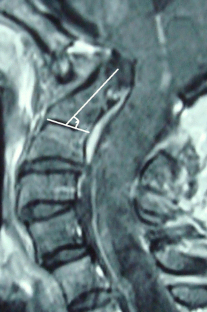

Sixteen adult patients with Chiari I malformation with significant ventral cervicomedullary compression, in the absence of BI, were included in the study. Atlantoaxial dislocation (AAD) was excluded in these patients by flexion-extension craniovertebral junction X-rays and computed tomography (CT). Their clinical profile, especially symptoms pertaining to cervicomedullary compression, i.e. dysphagia, dysarthria and spasticity, were graded. The ventral cervicomedullary compression (VCMC) was quantified using pBC2 (maximum perpendicular distance to the basion-infero posterior point of the C2 body) on sagittal magnetic resonance imaging (MRI) and only those patients with pBC2 ≥9 mm were included. Furthermore, retroversion of dens and retro odonotid tissue thickness was calculated in each patient. Fifteen patients underwent posterior decompression alone and one refused surgery. Follow-up was done every 3 months. Repeat MRI was done at 1 year following surgery to look for pBC2.

The mean pBC2 was 11 ± 0.2 mm. Retroversion of dens was responsible for VCMC in three patients and periodontoid crown in 13. There was no correlation between the tonsillar descent, age and the pBC2. All patients improved in symptoms of cervicomedullary compression following surgery. One patient worsened 6 months after initial improvement. The pBC2 did not change, as seen on follow-up MRI done in five patients.